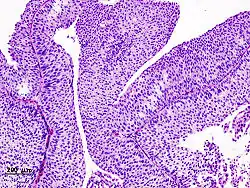

| Histopathology of transitional carcinoma of the urinary bladder. Transurethral biopsy. Hematoxylin and eosin stain. | |

The 1973 WHO grading system for transitional cell carcinomas (papilloma, G1, G2 or G3) is most commonly used despite being superseded by the 2004 WHO[14] grading for papillary types (papillary neoplasm of low malignant potential [PNLMP], low grade, and high grade papillary carcinoma). High-grade carcinoma typically displays more pleomorphism, multiple mitoses, euchromatin and relatively prominent nucleoli, and uneven distribution of nuclei.

Transitional cell carcinoma, being low-grade to the left, and high-grade to the right. H&E stain -

Papillary transitional cell carcinoma, low grade -

Histopathology of urothelial carcinoma of the urinary bladder, showing a nested pattern of invasion. Transurethral biopsy. H&E stain -

Histopathology of urothelial carcinoma of the urinary bladder. -

Micrograph of urethral urothelial cell carcinoma. H&E stain